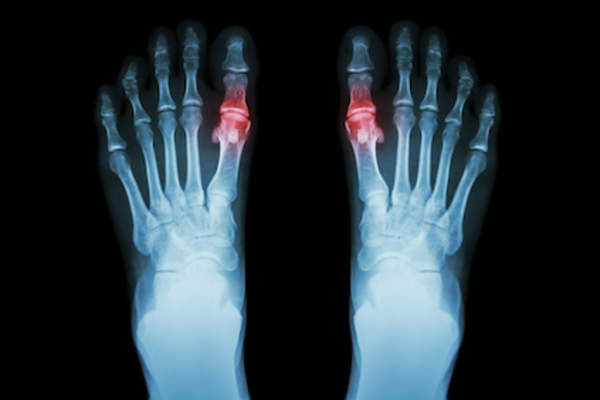

这是一种常见的和痛苦的疾病,是由于尿酸晶体沉积在关节处形成的。其原因是血液中尿酸过高,或高尿酸血症。结晶体积聚,导致关节疼痛的炎症发作。痛风的症状包括突然的剧烈疼痛在你的一个或多个关节里通常是在晚上。那个关节会发炎发红,简单的碰一下就会很疼。

痛风可以发生在任何地方尿酸已经沉积-在任何关节,肌腱或囊,或液体充满的囊。然而,尿酸往往沉积在较冷的地方,向身体的边缘。微创伤或轻微损伤往往会使身体的某些部位易受尿酸沉积的影响,然后在尿酸沉积的部位发作。大脚趾或大脚趾的底部符合这两个标准。痛风可以影响多个关节在同一时间,称为多关节痛风发作。